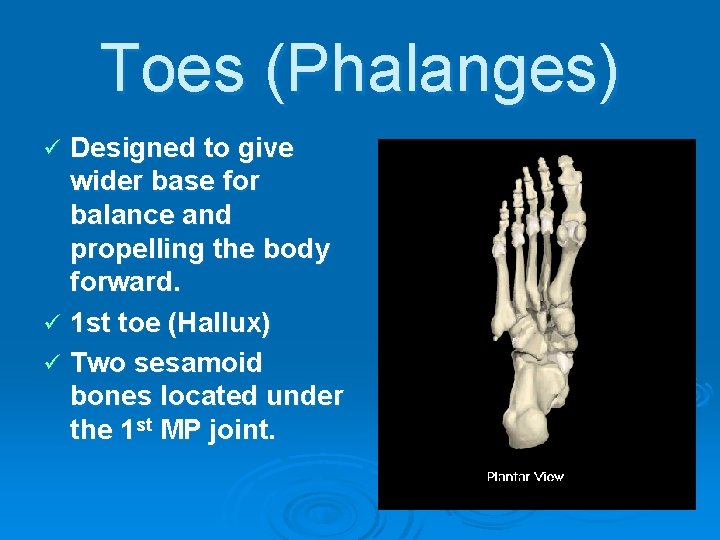

Toes (Phalanges) Designed to give wider base for balance and propelling the body forward. ü 1 st toe (Hallux) ü Two sesamoid bones located under the 1 st MP joint. ü